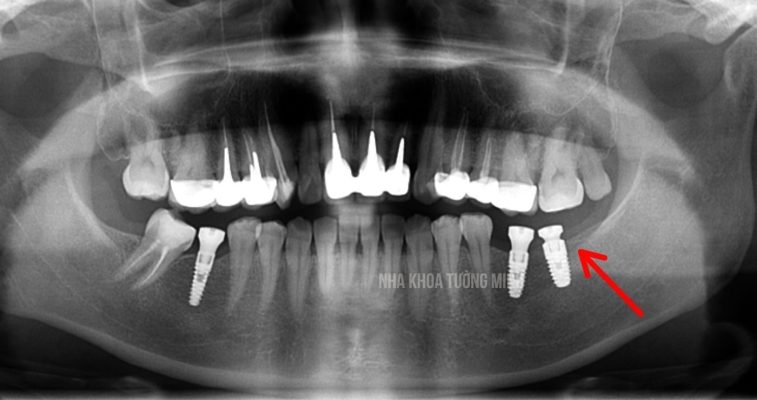

Vì sao nên cấy Implant riêng cho răng số 6 và 7?

Răng số 6 và 7 là răng hàm lớn, chịu lực nhai chính. Khi mất 2 răng này, việc cấy mỗi răng một trụ Implant riêng biệt mang lại hiệu quả tốt hơn.